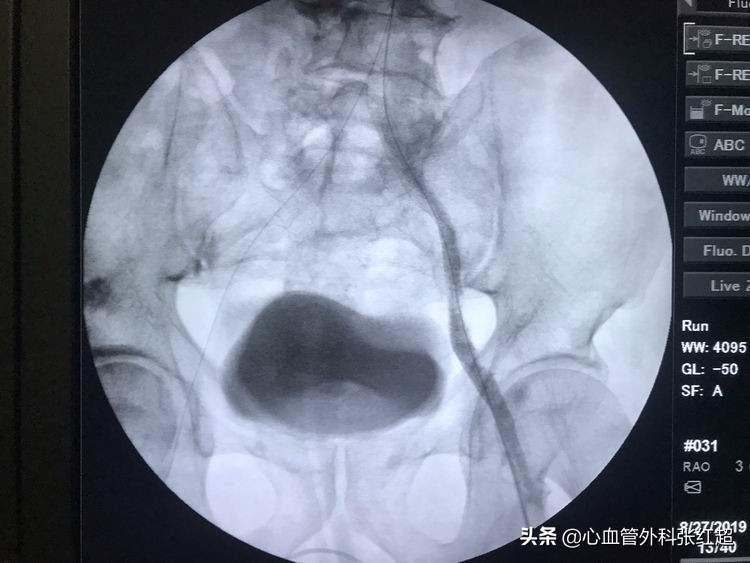

送入小球囊扩张,目的:①预防出血;②预防血栓脱落。

扩张时一定注意保持外鞘位置,避免血肿形成。

扩张中患者有痛应终止,防心弯曲部分球囊肩撕性撕裂。

血管造影剂排空快,对侧显影淡,说明血管内血流速度快。